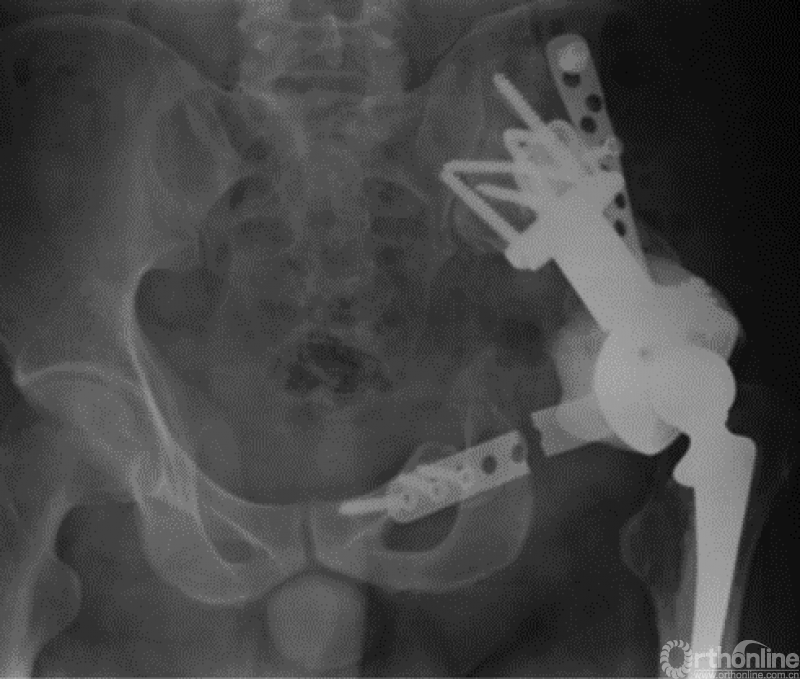

马鞍式假体未与宿主骨形成稳定的骨性连接,整体功能较差,并且并发症发生率较高[2-5](图1)。冰激凌假体与宿主骨的连接更加紧密,但不适合骨盆I区大部分切除的骨缺损,不能重建完整骨盆环[6-10](图2)。组配式半骨盆假体组装灵活,且可进行骨盆环完整重建,但其安装技术要求高,假体组件间存在断裂风险,不匹配得假体与宿主骨锚定将直接影响骨整合,最终易导致松动[1,11-15](图3)。

图3 组配式半骨盆假体